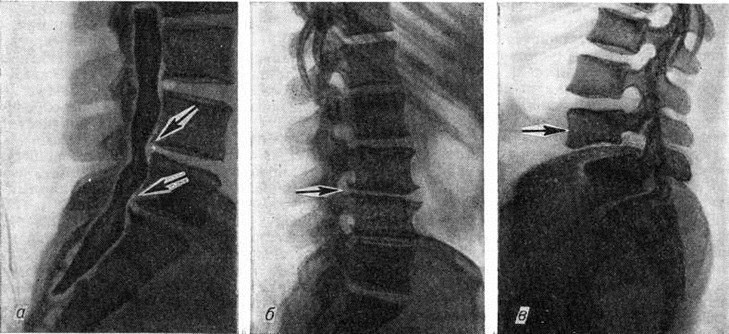

Объем рентгенологическое исследования в каждом отдельном случае следует определять индивидуально с учётом клинические проявлений болезни. Рентгенографию позвоночника обязательно производят в прямой и боковой проекциях. Для уточнения статических напряжений в позвоночнике желательна и рентгенография в положении больного стоя. В ряде случаев необходимы рентгеновские снимки с поворотом больного под углом в 45°, а также прицельные рентгенограммы в различных проекциях и томограммы. Для выявления нарушений подвижности в позвоночнике производят функциональное рентгенологическое исследование или рентгенокинематографию (смотри полный свод знаний). В диагностически трудных случаях, а также для уточнения показаний к оперативному вмешательству, выявления места, характера и его объёма показано контрастное рентгенологическое исследование — пневмомиелография (смотри полный свод знаний), миелография с рентгенопозитивными контрастными средствами, радиоизотопная миелография (смотри полный свод знаний), которые позволяют выявить изменения в позвоночном канале, не определяемые при спондилографии, например, в случаях блокирования субарахноидального пространства грыжей межпозвоночных дисков (рисунок 2, а).

Выявляемые рентгенологически признаки остеохондроза необходимо оценивать в совокупности с клинические, проявлениями. Анализ рентгенологическое симптомов — наличие заднебоковых остеофитов (рисунок 2, б), сужение Межпозвонковой щели или межпозвонкового отверстия, смещение позвонков — спондилолистез (рисунок 2, в), вертебральный артроз на уровне шеи, спондилоартроз (смотри полный свод знаний), изменение общих физиологический искривлений позвоночника — позволяет полноценно оценить состояние больного.